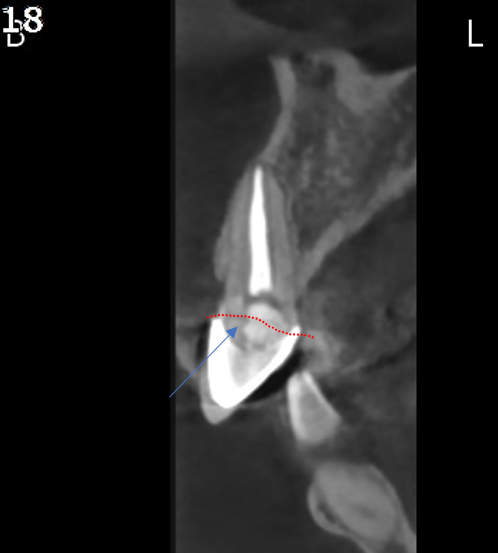

30대 남성분이 넘어져서 앞니가 흔들린다고 고촌치과에 내원하셨습니다.

CT 검사 결과 치아 머리 부분이 부러졌습니다.

살릴 수는 없는 상황이라 발치 즉시 임플란트와 즉시 임시치아를 계획하였습니다.